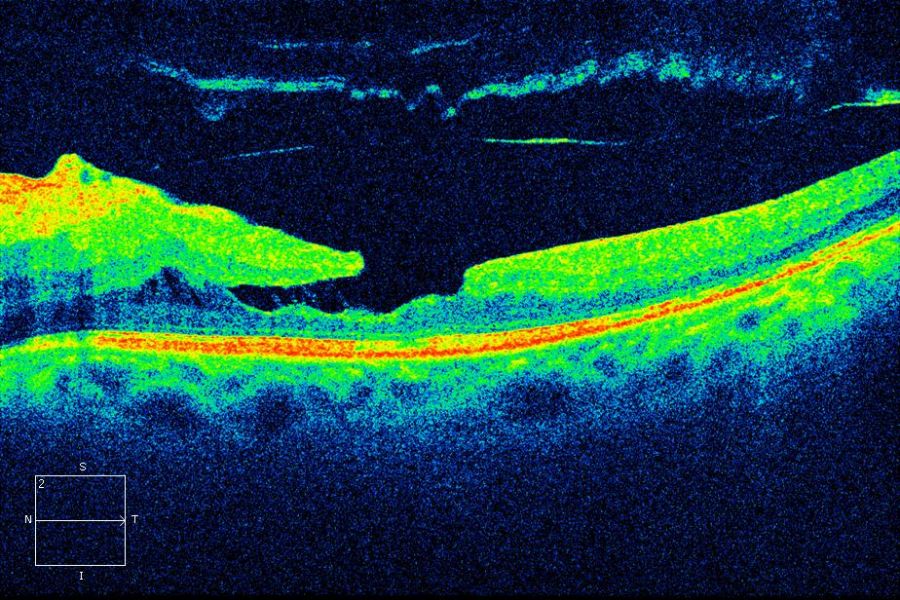

Maculaschichtforamen

MakulaschichtforamenПеревод

Английский | macular lamellar hole |

Английский | lamellar macular hole (аббревиатура: LMH) |